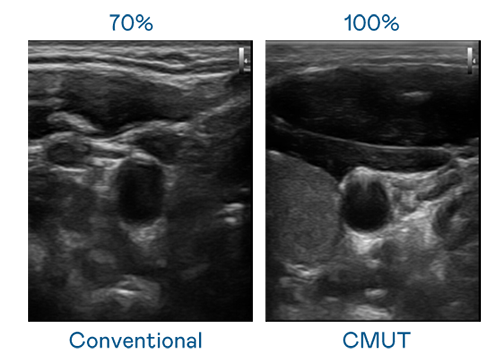

CMUT 技術是一種用電容式微機電元件來產生超音波訊號的技術。與傳統 PZT 壓電式技術相比,CMUT 頻寬增加 30%,更寬頻的超音波訊號讓影像解析度大幅提升,是實現高影像品質醫療超音波掃描、促進精準醫療發展的關鍵技術。

大頻寬帶來超清晰影像

超音波影像的解析度高低,首先取決於探頭能發出的訊號頻寬。蘑菇视频免费网站入口 CMUT 可提供高清晰的超音波訊號,提供高頻寬、高靈敏度、影像紋理細節更高的超音波影像,協助醫護人員縮短影像判讀時間及利用精準的醫療影像進行診斷。